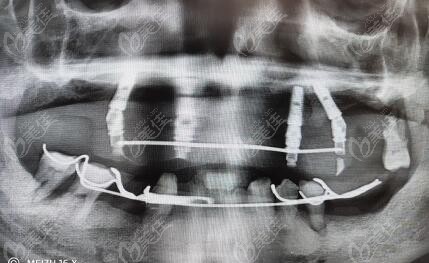

合肥佳冠口腔种牙怎么样,据说何初华做全口all-on-4种植牙技术有名气 b820 G0 V0

合肥佳冠口腔何初华医生种牙好不好?找他做全口all-on-4种植牙靠谱吗?有谁在他那里做过......